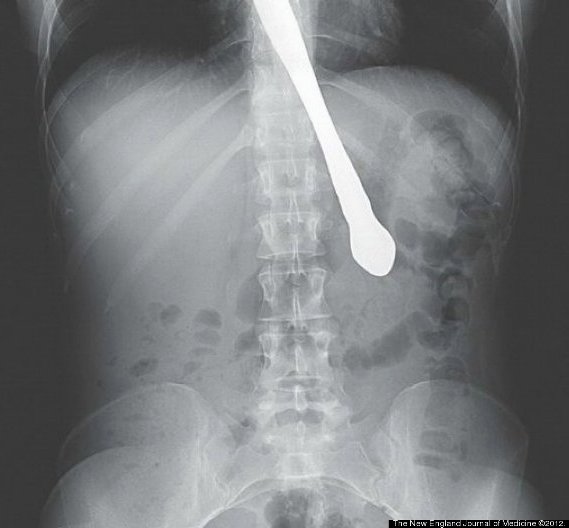

butter knife

A 30-year-old Atlanta woman with a history of bulimia swallowed a knife while demonstrating that she no longer had a gag reflex for friends, according to the New England Journal of Medicine.